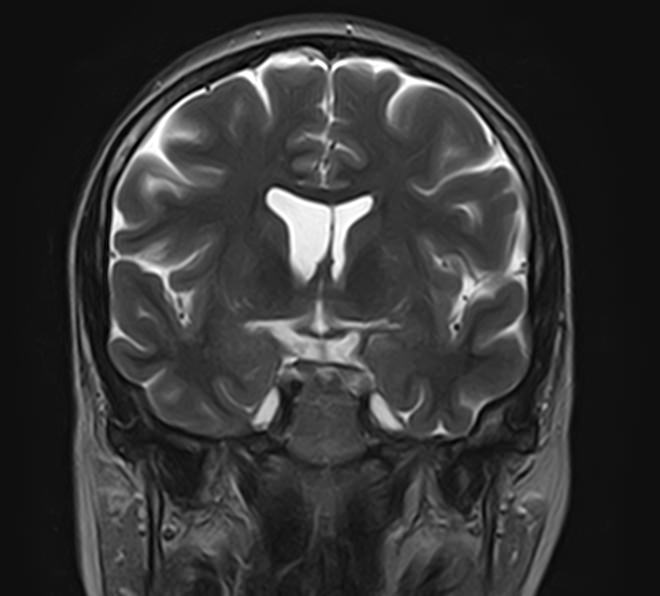

Стандартная МРТ головного мозга дает важную информацию о состоянии и структуре мозговой ткани для выявления большого числа заболеваний, в том числе опухолевых образований, демиелинизирующих заболеваний, воспалительных процессов головного мозга и мозговых оболочек. Стандартную МРТ головного мозга дополняет МР-ангиография, которая отображает состояние системы кровоснабжения головы и шеи. Компьютерная программа обрабатывает данные, полученные при сканировании, и формирует объемные изображения как самого мозга, так и сосудистой системы в отдельности без прилегающих тканей. Обе методики применяются одновременно и взаимодополняют друг друга, давая полную диагностическую картину.

Исследование предоставляет информацию о состоянии тканей головного мозга и оболочек, проходимости кровеносных сосудов, наличии и размерах опухолей, тромбов, гематом и других патологий. Изучив изображения, нейрохирург или другой специалист получает информацию о локализации патологии, степени повреждения тканей мозга, может принять решение о проведении операции либо контролировать ход лечения.